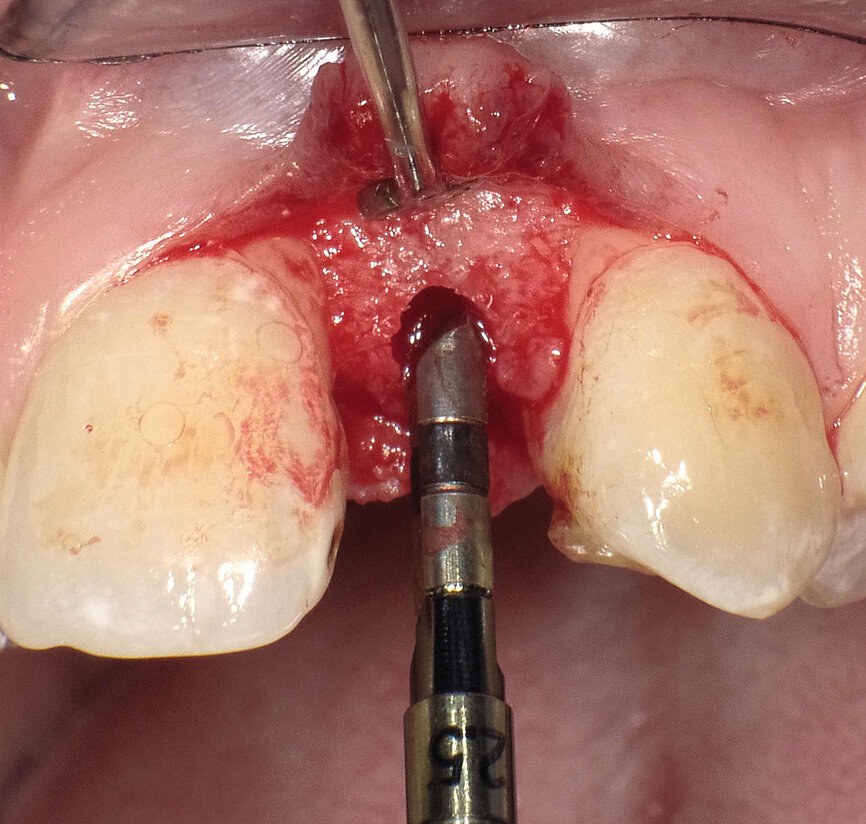

Fig. 3 : Un alésoir manuel de Ø 2,5 mm est utilisé pour élargir l’ostéotomie initiale préparée au moyen du forêt-guide à grande vitesse.

|Fig. 4 : Le dernier alésoir manuel de Ø 3 mm est prudemment introduit à la main entre les deux racines. La partie tranchante est dirigée vers la corticale palatine et l’axe de rotation est à un maximum de 45°.

La technique d’ouverture de l’espace inter-radiculaire consiste à exercer une légère pression de façon à écarter les deux racines qui bornent un espace interradiculaire étroit, au moyen d’un instrument spécial. Les alésoirs manuels (Bicon Dental Implants) comportent une extrémité pourvue d’arêtes tranchantes verticales se terminant en pointe, et une queue cylindrique non coupante qui sert d’extension. Les alésoirs manuels sont introduits manuellement dans l’ostéotomie initiale à l’aide d’une poignée de serrage droite filetée. Cette ostéotomie est effectuée avec un foret-guide ordinaire de Ø 2 mm (à 1 100 tr/ min) jusqu’à une profondeur de 3–4 mm seulement. Dans ces cas, l’utilisation de fraises à haute vitesse pourrait causer un traumatisme en provoquant une surchauffe du desmodonte, avec le risque de léser l’une des racines. L’ostéotomie initiale, d’une largeur de 2 mm et d’une profondeur de 3–4mm, est suffisante pour permettre l’insertion de l’alésoir manuel de Ø 2,5 mm entre les racines. Il ne faut pas oublier deux points importants : d’une part, les 3 mm constituant l’extrémité de l’alésoir dans la partie apicale sont coniques et que leur diamètre est donc inférieur à celui du corps de l’alésoir et, d’autre part, les arêtes tranchantes ne sont utilisées que pour ouvrir le passage le long de la corticale palatine plus épaisse. Il est possible d’introduire la queue cylindrique non coupante de l’alésoir dans l’os spongieux et entre les deux racines sans les léser, puisqu’il n’y a ni couple d’insertion ni coupe intervenant au cours de cette procédure. Le dernier alésoir manuel de Ø 3 mm a également été inséré dans l’ostéotomie et positionné entre les racines. Une pression continue a lentement été appliquée sur la poignée de serrage droite. Parfois, il est nécessaire d’utiliser un maillet pour faire avancer l’alésoir jusqu’à une distance de 10 ou 11 mm par rapport à la crête (Figs. 3 et 4).